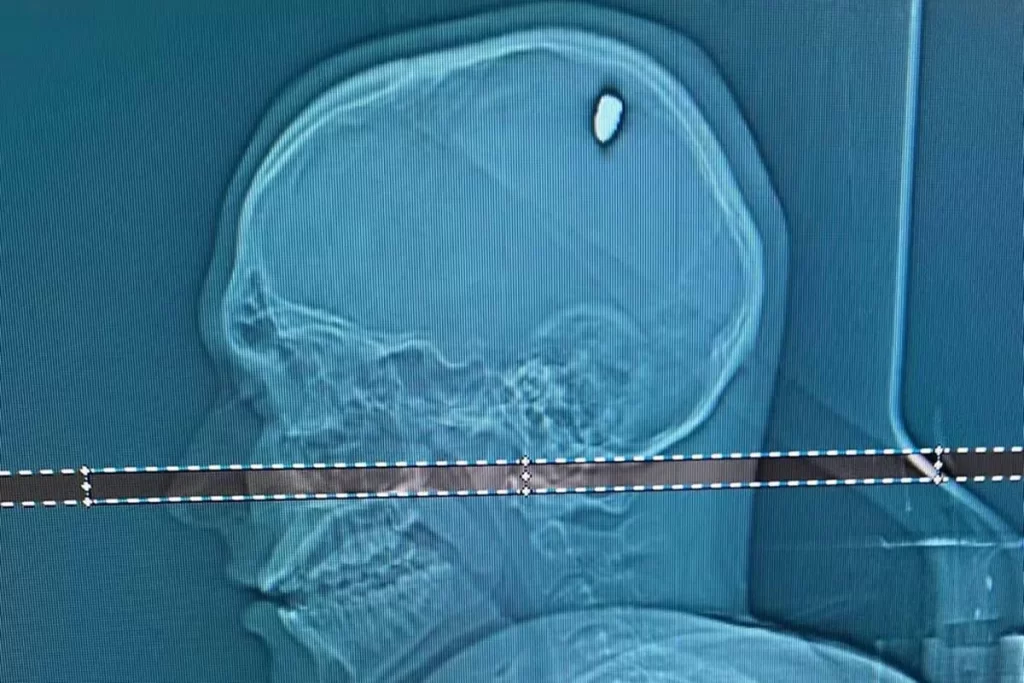

Um exame de tomografia mostrou que Mateus estava com uma bala alojada na cabeça. “Parte dela penetrou no cérebro. Isso causou compressão da região, e os movimentos involuntários do braço”, explica o neurocirurgião Flávio Falcometa.

“Por poucos milímetros, ela poderia causar um dano bem mais grave, como ficar com o braço paralisado ou metade do lado do corpo paralisado. Foi arriscado, bem arriscado para o paciente. A gente acredita que em 20, 30 dias, ele vai seguir com a vida normal dele”, completou o neurocirurgião.